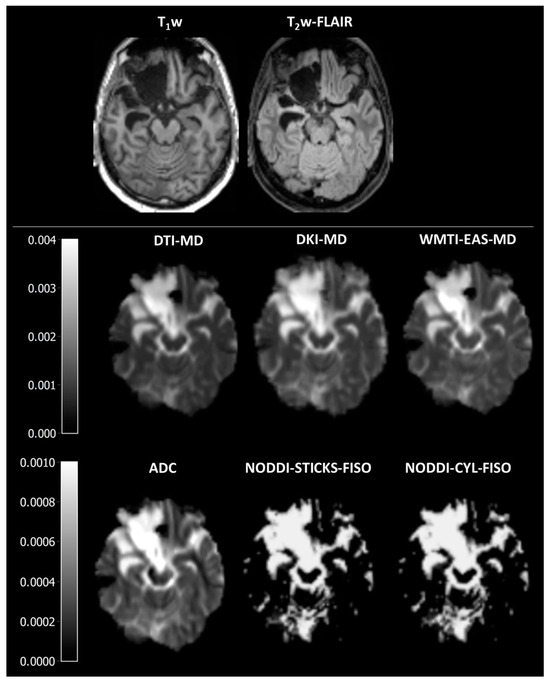

Figure 1. Representative images of axonal fibre-bundle integrity parameters. DTI-FA is fractional anisotropy as estimated using diffusion tensor imaging, DKI-FA is fractional anisotropy as estimated using diffusion kurtosis imaging, FBA-FD is fibre density as estimated using fixel-based analysis, WMIT-AWF is axonal water fraction as estimated with white matter tract integrity, NODDI-STICKS-FICVF is the intracellular volume fraction as estimated using the neurite orientation dispersion and density imaging with the sticks model for neurites, and NODDI-CYL-FICVF is the intracellular volume fraction as estimated using the neurite orientation dispersion and density imaging with the cylinder model for neurites.

As a sanity check to assess whether the various methods displayed discrepant results in correspondence with the different tissue composure, the values of the various parameters were compared between surgical cavity, peri-surgical cavity, NAWM, and WM. As expected, all parameters were significantly different between different tissues (H = 40.4–42.2, p < 0.001, Figure 1 and Figure 2A, Supplementary Tables S1 and S2, Supplementary Figures S1 and S2). Aside from WMTI-IAS-Da, all parameters had a gradient of low/absent in the surgical cavity, higher in peri-surgical cavity, and highest in NAWM and WM (Supplementary Tables S2 and S3).

To determine the agreement between the various DWI methods, the correspondence between them was assessed. All methods strongly correlated with each other (r = 0.77–1.00, Figure 3A, Supplementary Table S4), except for WMTI intra-axonal diffusivity (r = 0.05–0.30). Furthermore, a low bias as depicted by differences in slope and ICC was observed (Figure 3A and Supplementary Table S5) between DTI-FA, DKI-FA, WMTI-AWF, and FBA-FD, and between NODDI-STICKS-FICVF and NODDI-CYL-FICVF, but with a high bias between the two groups. When compared to each other, the methods were significantly different from each other at a group level (H = 9609, p < 0.001, Table 3, Supplementary Tables S2 and S6). Bonferroni-corrected post hoc tests showed that all were different except for DTI-FA from DKI-FA (H = 126, p = 1.000), NODDI-CYL-FICVF from NODDI-STICK-FICVF (H = 162, p = 1.000), and DKI-FA from WMTI-AWF (H = −357, p = 0.076), as determined via Bonferroni-corrected post hoc tests. These findings suggest that while the absolute values were statistically different from each other, the relative change in parameters between the different ROIs was similar for all axonal fibre-bundle integrity parameters (except WMTI-IAS-Da).

In general, the different DWI models have a high correspondence with each other, as displayed by the strong correlations. The only discrepant result is in this case WMTI-IAS-Da, which is the intra-axonal diffusivity. This parameter is high in the surgical cavity, medium-high in the peri-surgical cavity, and low in the NAWM and WM. As this parameter is supposed to depict the diffusivity within axons, and no axons are present in the surgical cavity, and there is a high abundance in the WM, this finding is rather unexpected. In the documentation of PyDESIGNER, there is no information regarding the calculations of WMTI [28], and neither is there in the original DESIGNER article [31]. However, in the DESIGNER article, the authors cite Fieremans et al. for the WMTI model [11,31]. Therefore, we assume that the developers of PyDESIGNER used the Fieremans model. In the study of Fieremans et al., WMTI-IAS-Da is the trace of the intra-axonal diffusivity, thus the summation of the intra-axonal eigenvalues [11]. While the article of Fieremans shows similar patterns of WMTI-AWF and WMTI-IAS-Da, this correspondence is clearly absent in the results of PyDESIGNER. This difference suggests an erroneous implementation of the WMTI-IAS-Da calculation in PyDESIGNER (Supplementary Figures S1 and S2). Surprisingly, WMTI-AWF generated with PyDESIGNER corresponds with physiological expectations and also with axonal fibre-bundle integrity parameters derived from other DWI models (Figure 1 and Figure 2).